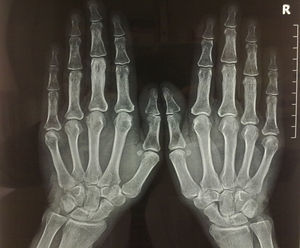

Con la sospecha de enfermedad de Paget se solicitó una gammagrafía ósea con Tc-99 (fig. 2), en la que se apreció un aumento de captación en la vértebra D 10, tercera articulación interfalángica proximal izquierda, pelvis y fémur izquierdo. Se solicitó radiología simple de las regiones captantes, destacando la afectación de la tercera falange de la mano izquierda, siendo el resto de la imagen radiográfica normal (fig. 3).